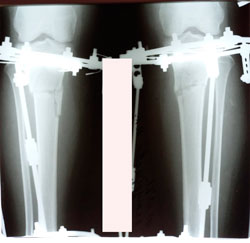

Исходник - 34 года.

Дата операции - 10.02.2021